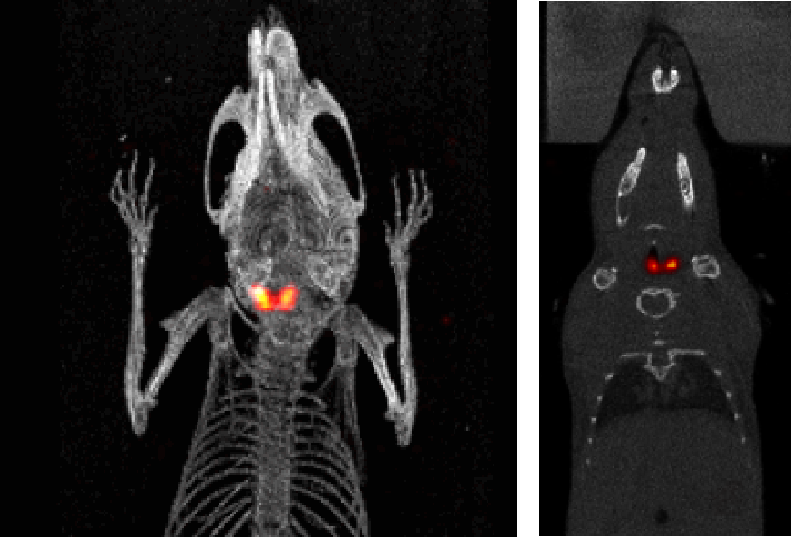

1、神經(jīng)系統(tǒng)SPECT成像

大鼠腦部SPECT成像:99mTc-HMPAO:腦血流灌注顯像劑,用于腦血管疾病,腦外傷,癲癇,癡呆癥,腦死亡的診斷;用于精神疾病的腦功能及正常腦生理功能活動(dòng)的研究。進(jìn)入腦組織的99mTc-HMPAO構(gòu)型改變而轉(zhuǎn)變成水溶性化合物,無法再次通過血腦屏障而滯留在細(xì)胞內(nèi),因此能在腦內(nèi)長(zhǎng)時(shí)間滯留。120 MBq,30 min uptake,30 min SPECT。

神經(jīng)系統(tǒng)成像.jpg